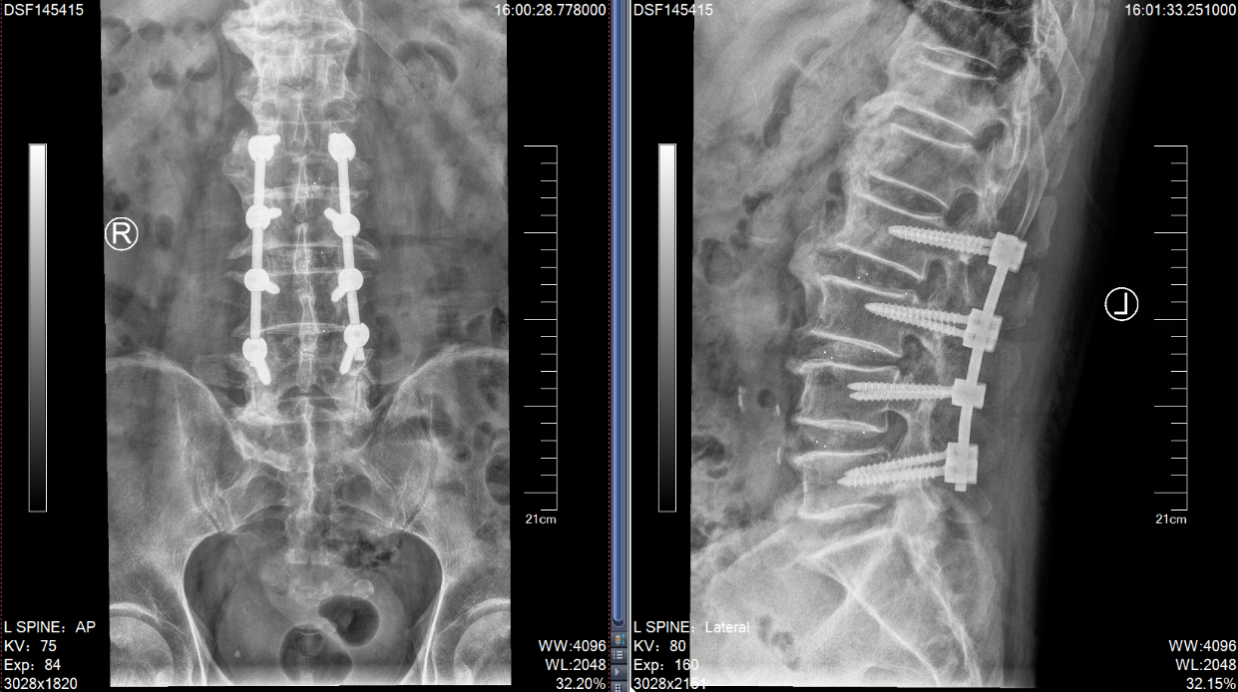

张老爷子今年84岁高龄了,家住盐城建湖。之前老人家身子骨一直硬朗,吃得好,睡得香,直到近年腰腿痛再次发作,如今已经发展到了几乎寸步难行的程度。说起来,这位老爷子算是姜主任的“老熟人”了,二十多年前他就曾因“腰椎间盘突出症”在苏州接受过姜主任的手术,术后恢复良好。但近几年,随着年龄增长,老爷子的腰椎疾患又犯了,且加重很快。这次在他两个儿子的陪同下,特地从外地赶来独墅湖医院,希望姜主任能给他解决病痛。姜主任仔细检查后发现:老先生腰椎退变严重,患的是一种名叫“腰椎管狭窄症”的疾病。表现为“腰腿痛”和“间歇性跛行”的症状,需要做彻底的“椎管扩大减压+椎弓根螺钉内固定+椎间融合术”。刚讨论完老先生的病情,患者的小儿子说:“给我哥看看吧,他也挂了您的号,是颈椎病,可能也要手术。”姜主任分析过病情后确认患者得了一种称为“后纵韧带骨化症”的颈椎病,几年前就已确诊,因为害怕手术不成功会导致瘫痪,一直拖到现在,已经严重到难以独立行走。这次下定决心与老父亲一起来苏州接受手术。由于床位紧张,老先生首先住进医院接受了手术。手术很顺利,术后仅仅两天,他已经可以下床活动,双下肢症状明显缓解。

(腰椎MRI提示L2-5椎间盘突出,椎管狭窄明显)

(术后复查腰椎X片:此次对患者进行了L2-5的椎管扩大减压+神经根松解+椎弓根螺钉固定+椎间融合术)